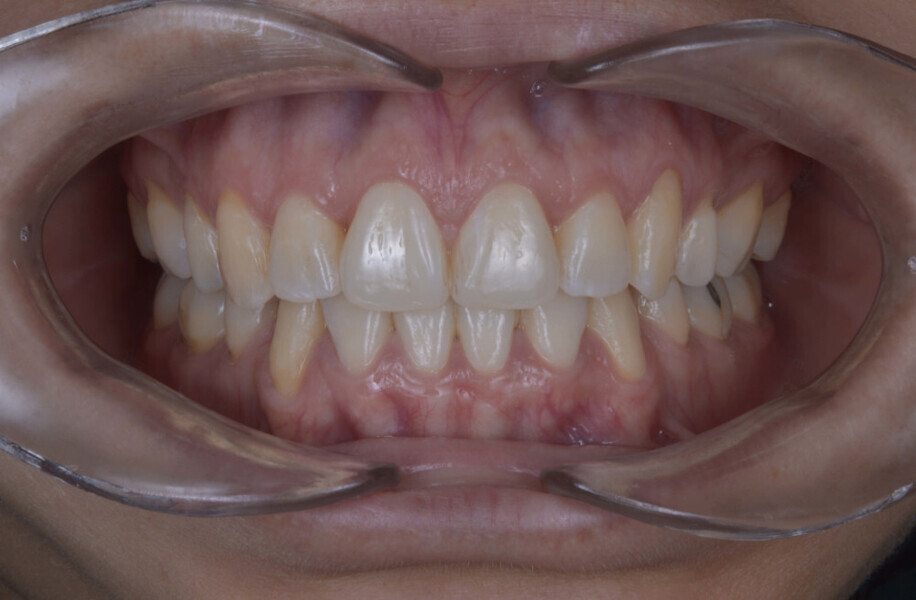

Before the aligner treatment began, the maxillary and mandibular second premolars were extracted to create space. With orthodontic treatment, distalisation of the anterior teeth was achieved by employing maximum mandibular anchorage and moderate maxillary anchorage (Figs. 5–7). At the end of the treatment, a stable bilateral Class I occlusion had been achieved, as well as normal inclination and retrusion of the anterior teeth, consequently improving the profile (Figs. 8–10).

At the end of the treatment, the patient showed a significant improvement in her profile thanks to the orthodontic treatment (Fig. 11) and an improvement in her facial shape thanks to the injection of botulinum toxin into the elevator muscles (Fig. 12). She also had a decrease in bruxism and its symptomatology thanks to the combination of both treatments.